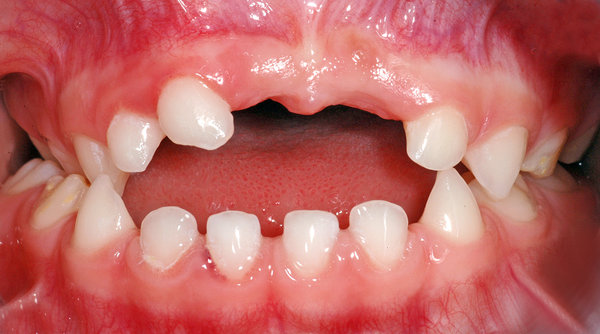

Anbei ein Fall einer 4½ Jahre alten Patientin, die Befunde in folgenden Bereichen aufzeigt: Unfallfolge mit Zahnverlust ( Punkt 1), überzählige Zähne (Punkte 2 und 3), Zahnstellungsabweichungen (Punkte 4 und 5).

- Vorzeitiger Verlust von zwei oberen mittleren Milch-Schneidezähnen infolge eines Sturzes (der rechte, 51, wurde direkt nach dem Sturz entfernt, der linke, 61, musste etwa 6 Monate danach entfernt werden, da sich im Knochen an der Wurzel eine Entzündung gebildet hatte). Beide Zähne sind auf dem klinischen Bild schon nicht mehr zu sehen. Die Entzündung im Knochen und die vorzeitige Auflösung der Wurzel des Zahnes 61 sind auf dem Röntgenbild 1 mit schwarzen Pfeilen markiert.

- Überzähliger seitlicher Milch-Schneidezahn rechts (52'); siehe dazu auch den Beitrag zu überzähligen Zähnen.

- Kreuzbiss im Seitenzahnbereich auf der rechten Seite (blaue Pfeile im Bild).

- Offener Biss in der Front (das heisst, dass die Schneidezähne beim Zusammenbeissen nicht «übereinander» oder aneinander kommen; ist im Bild blau markiert).

Klinisches Bild

Ansicht von vorne. Darauf sind die Zahnstellungsabweichungen und der überzählige Zahn zu sehen. In den weiteren Bildern sind die Befunde markiert.

- Ansicht von vorne, klinisches Bild